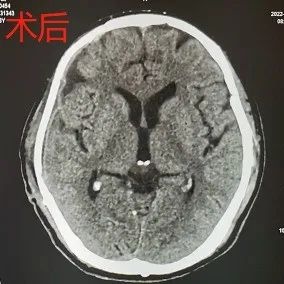

22.01.22,应家属要求,完善术前检查后,行“右侧颅骨修补术”。

手术后